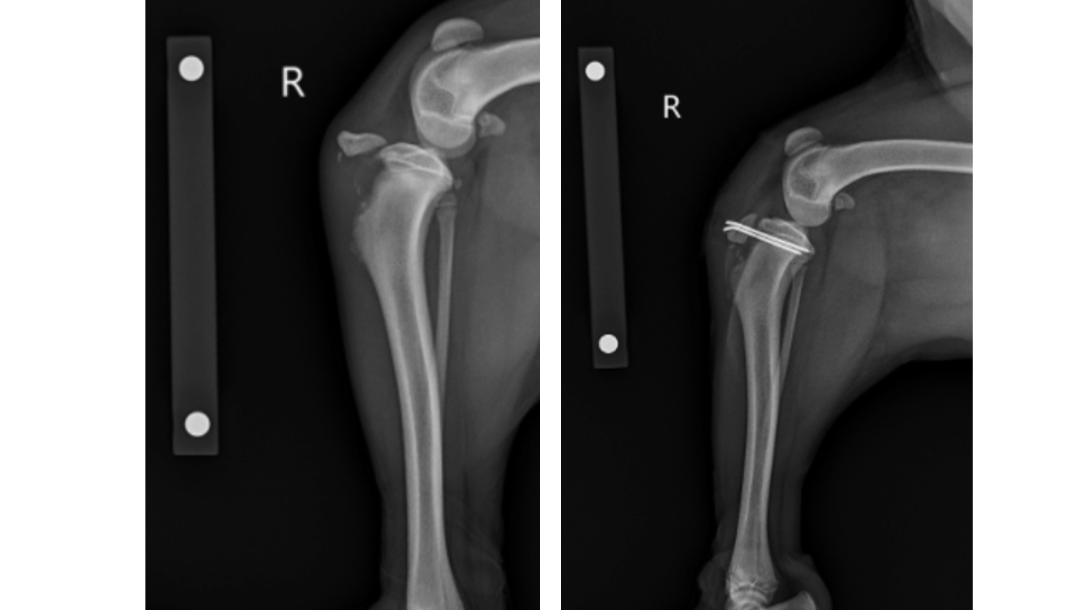

This past weekend, Ranger got a little too excited and tried to jump onto the bed, which was too high for him. He fell backward onto the ground, landed hard on his back right leg, and was unable to put any weight on it after that. With only two good legs, he hasn’t been able to stand or walk on his own since the accident, though we can tell that he wants to. After a long day in the ER, he was able to get X-rays taken and was found to have a fracture called an acute tibial tuberosity avulsion (pictured below). Unfortunately, this type of fracture requires surgery to heal and recover properly, and with only three legs to begin with, Ranger needs all those legs functioning as best as possible! Ranger was able to get in for surgery on Thursday (8/25) & everything went smoothly! He stayed at the veterinary center overnight so they could continue his post-op care, and we were told that he earned himself a little fan club during his stay. We brought him home Friday afternoon and he will now begin the 6-week recovery process while his leg fully heals. Below is his leg before (left) & after (right) the surgery.